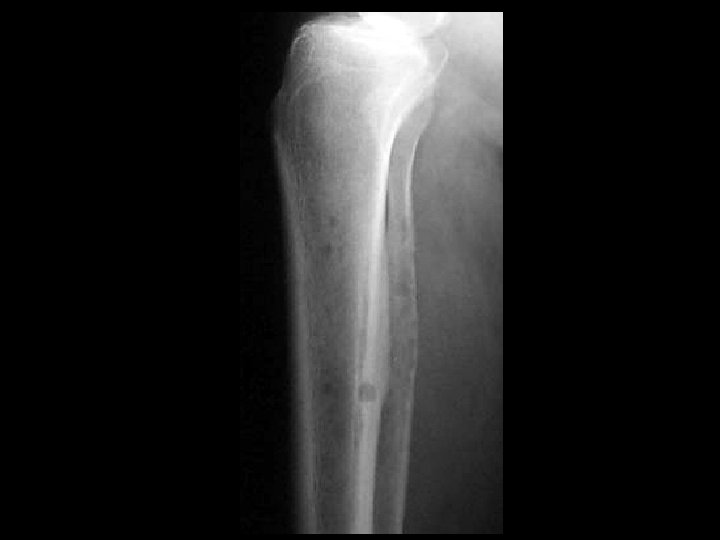

Langerhan’s cell histiocytosis • Findings: – Predominantly lytic lesion of the tibia with cortical thickening, periosteal reaction, and soft tissue swelling and edema • ddx: – Infection – Ewing’s sarcoma – Lymphoma